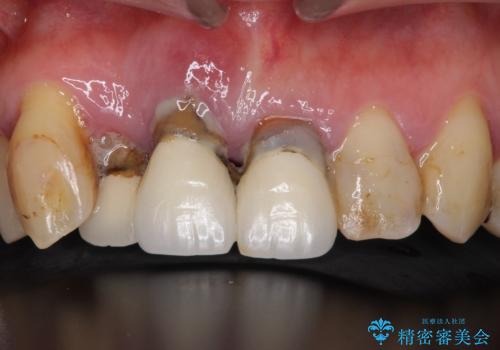

- 上顎前歯をきれいにしたいとのことで来院されました。

レントゲンを撮影すると保存が難しい歯がありました。

またがたつきの度合いから歯を1本抜歯して矯正治療を行いセラミックブリッジを装着することで、審美的・機能的改善を行う計画としました。